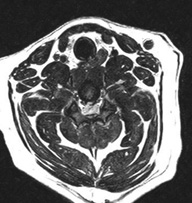

胸髄髄内腫瘍